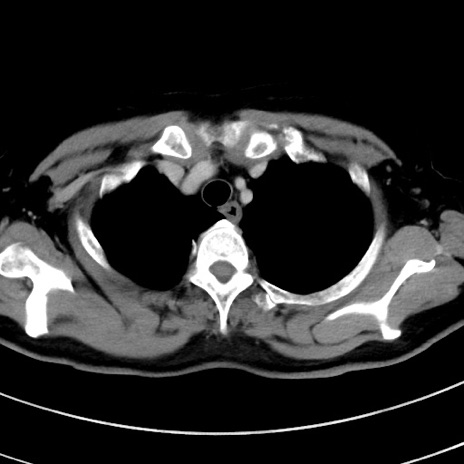

症例9(横断像)

【症例】 60歳代女性

【主訴】むかつき、みぞおちの痛み

【現病歴】3日前よりむかつきがあり、食事がとれない。

【既往歴】糖尿病

【身体所見】発熱なし、心窩部圧痛軽度あるも、腹膜刺激症状なし。

【データ】WBC 7400、CRP 1.92